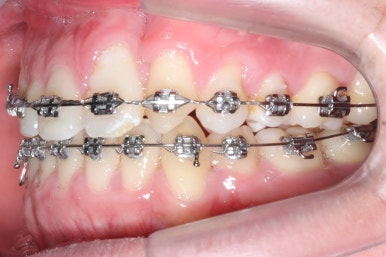

악궁확장과 동반하여 부산구순구개열 키다리아저씨치과에서는 브라켓을 부착하여 가지런하게 하는 작업을 시작하였습니다.

위아랫니가 각각 가지런해지고 있는 것을 볼 수 있습니다.

윗니는 아직 가지런하게 하는 작업 중이며, 아랫니는 가지런하게 하는 작업은 거의 다 되었습니다.

계속 윗니는 가지런히 해주고 있으며 아랫니는 앞뒤를 뒤로 당기고 있습니다.

거꾸로 물리던 앞니가 서서히 개선되어 가는 것을 볼 수 있습니다.

부산구순구개열 키다리아저씨치과에서 교정치료 하신지 1년여만에 드디어 앞니는 거꾸로 넘어왔고, 윗니들도 상당히 많이 가지런해졌습니다.

이 뽑은 자리도 상당히 많이 줄어든 것을 볼 수 있고, 이제는 정상적인 포개짐이 만들어졌습니다.